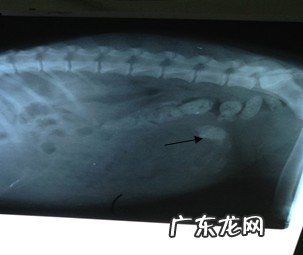

X光查验:除显著十二指肠排泄物外,肠道内脏东西(箭头符号所说处)

文章插图

肠道内脏东西